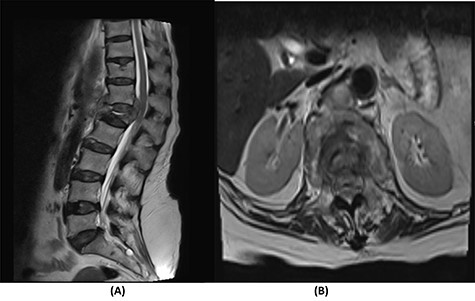

Fourteen months later, the patient presented to the ED complaining of generalized body pain associated with malaise. The neurological examination was unremarkable. An MRI of the lumbar spine showed recurrence of the lesion with loosening and pullout of the implant, kyphosis and dislocation, with cord compression and collection (Fig. 2). Computed tomography (CT) scan showed a burst fracture of the L1 vertebra with loose screws (Fig. 3). CRP was 21 mg/l, ESR was 115 mm/h and procalcitonin was 0.051 ng/ml. The decision was made to do a CT-guided biopsy from the left paraspinal mass of T12–L1. The tissue biopsy was subjected to TB-polymerase chain reaction testing and acid-fast bacillus culture; both results were positive for M. tuberculosis. The patient was diagnosed with TB spondylitis and was started on the full anti-TB four-drug regimen.

(A) T2-weighted sagittal spine MRI demonstrating changes at the thoracolumbar spine with previous decompression for pathological fracture of L1 vertebra. There is interval progression of the disease with a soft tissue mass at the previous site extending to the prevertebral and epidural spaces, compressing the neural element. (B) T2-weighted axial spine MRI of the corresponding level of L1 vertebral body.